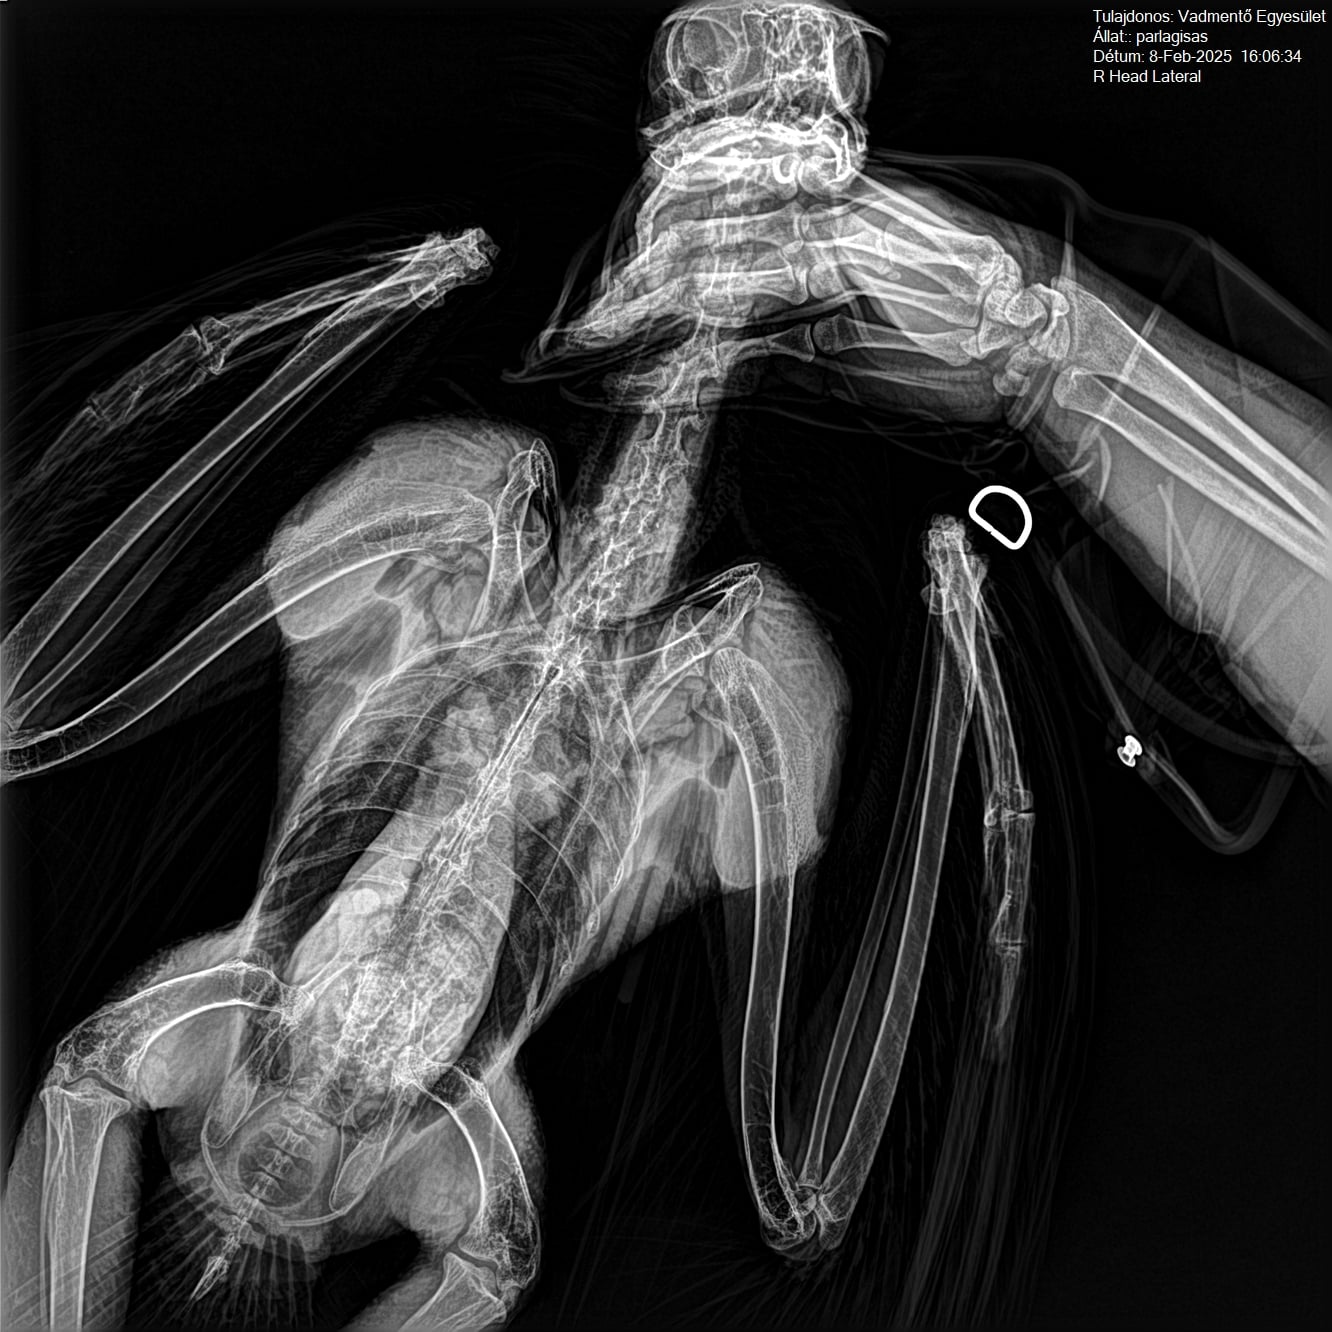

Nehéz szavakba önteni azt az érzést, amit akkor éreztünk, amikor a sas a gondozásunkba került. Hatalmas bizalmat kaptunk azzal, hogy gondoskodhattunk róla – ez egyben óriási kihívás is volt, hiszen nagyon legyengült állapotban érkezett hozzánk.

A mai nap azonban ünnep: a parlagi sas újra szabad! Felemelő érzés látni, ahogy ereje teljében, önállóan szárnyra kapott. Ég veled, tollas barátunk – szállj csak, szállj, égi vadász!